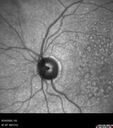

wet AMD - Classic CNVM mild vision loss

80 year old female She did not notice a problem but then when she saw you her vision in the right eye was hazy. The left eye was being watched because of eyelid herpes. The right eye has always been the weaker eye. She has not noticed a vision change in the right eye.

VA OD: Dcc20/40+1 NccJ3

VA OS: Dcc20/25-2 NccJ1-1

Vision improved to 20/25 after two Avastin shots and at 1 year she is getting treatment every 2 months

Wet age-related macular degeneration - Classic Juxtafoveal Choroidal Neovascular Membranevu 290 fois80 year old female with mild vision loss. 20/40 OD, 20/25 OS. Avastin controlled disease. VA improved to 20/25 after 2 injections. At 1 year she is getting every 2 months treatment     (0 votes)